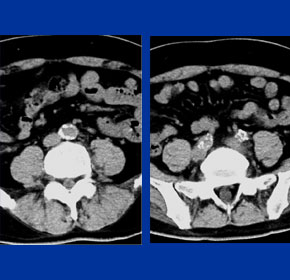

症例5

74歳 男性

【主 訴】

検診異常, 間歇性跛行

【起始・経過】

かねてより、100mの間歇性跛行。

平成11年、腹部大動脈瘤を指摘された。

平成18年1月CTにて増大傾向を認め当院紹介受診。

AAA size 5.2 cm

【既往歴】

74歳 HCC→TAE

高血圧(+) 糖尿病(−) 喫煙歴(−)

【治療計画】

AAA stent graft(Cook Zenith) + Lt iliac stenting + Lt internal iliac embolization

Pre-operative CAT scan